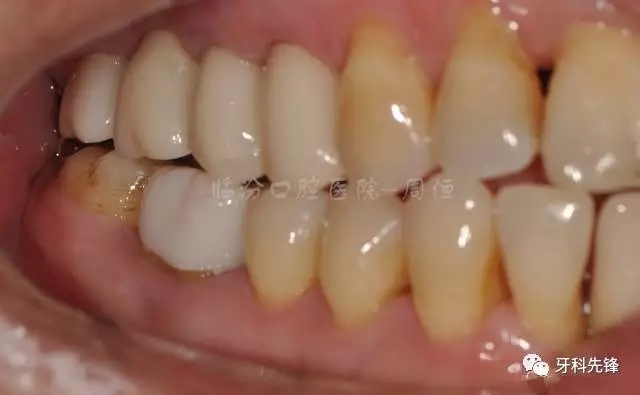

圖22烤瓷冠咬頜照

圖23烤瓷冠頰面觀